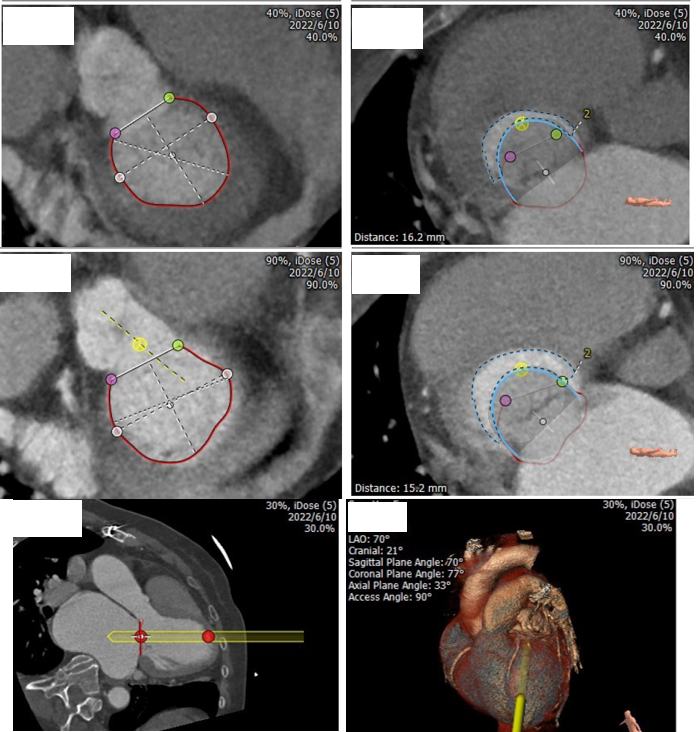

经过浙一心外科MDT团队综合讨,论评估患者病情后,由于缺血性心肌病、心功能储备极差、外科手术风险高。决定进行极其微创的经导管二尖瓣置换,采用以心医疗自主研发的MitraFix®经导管二尖瓣植入器械。术前CTA测算瓣环AP径29.6mm 、CC径37.2mm、 周长获得直径34.8mm 、使用MitraFix®29#瓣膜 Neo LVOT面积可。各项参数完全符合核心实验室入选标准。

经过浙一心外科MDT团队综合讨,论评估患者病情后,由于缺血性心肌病、心功能储备极差、外科手术风险高。决定进行极其微创的经导管二尖瓣置换,采用以心医疗自主研发的MitraFix®经导管二尖瓣植入器械。术前CTA测算瓣环AP径35.9 mm 、CC径36.6 mm、 周长获得直径37.9mm、使用MitraFix®34#瓣膜 Neo LVOT面积可。各项参数完全符合核心实验室入选标准。